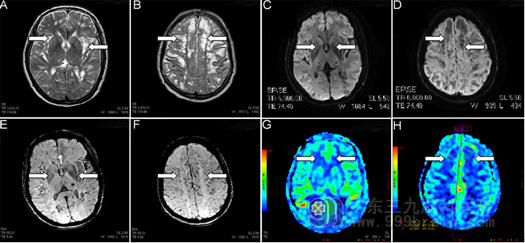

完善相关检查:血常规生化无明显异常;前庭功能检查提示:1.异常视频眼震图;2.位置试验阳性;颅脑MR提示:双侧大脑半球皮层及皮层下白质多发异常信号影,性质待定(图1A,B)。

根据患者症状及检查,明确诊断为:良性位置性眩晕,经过复位后头晕明显好转。但颅内多发病变性质不明,予以进一步完善弥散检查上述病变区亦示多发斑点状极低信号,余平扫病变呈SWI及DWI稍低信号,ADC图呈高信号,额叶病变ADC值为(2.25±0.49)×10-3mm2/s。(图1C,D);颅脑磁敏感成像提示:右侧小脑、双侧基底节区、双侧丘脑、左侧额叶、双侧顶枕叶多发含铁血黄素沉着可能性大(图1E,F);磁共振灌注成像:双侧额顶枕叶、双侧小脑半球弥漫性低灌注改变,考虑存在缺血改变(图1G,H);磁共振波谱分析:左侧半卵圆中心、左侧侧脑室前角旁病灶感兴趣区N-乙酰天冬氨酸峰均有不同程度降低,考虑存在神经元缺失。侧脑室旁异常信号影最终明确诊断为颅内巨大血管周围间隙。